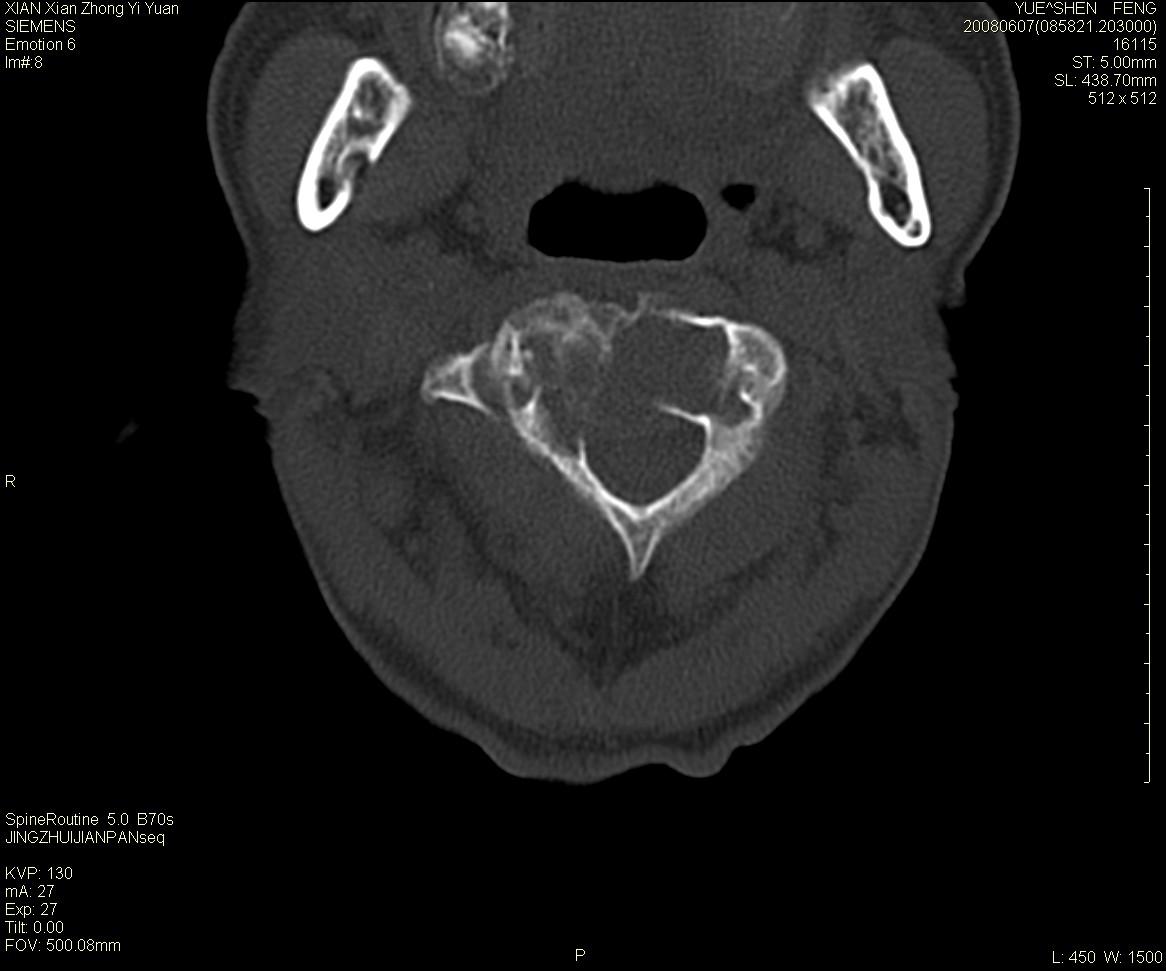

标题: CT13889:M72,颈部疼痛两年,近来加重。 [打印本页]

标题: CT13889:M72,颈部疼痛两年,近来加重。

枢椎囊状膨胀性改变,边缘锐利,周围无软组织肿块,考虑骨巨细胞瘤可能。转移瘤破坏膨胀性改变较轻。

作者: XIANXIANZHONGYI    时间: 2008-6-9 18:06

考虑浆细胞瘤

依据:

1 老年男性,颈部疼痛两年余。

2 ct:枢椎椎体显示膨胀性溶骨性骨质破坏,受损区域较大,边界清晰,其中似可见有小囊状结构,并残存有少量的骨小梁。病变与正常骨组织之间有一狭窄的分界区。受损部位部分边缘显示轻度骨质硬化。病灶突破骨皮质并在椎管形成软组织肿块影。

影像学检查:骨骼x线表现为单一部位的溶骨性改变,受损区域较大,边界清晰,其中可见有小囊状结构,少数可残存有少量的骨小梁。病变与正常骨组织之间有一狭窄的分界区。部分患者可见到病理性骨折,少数表现为受损部位的骨质硬化。ct和磁共振(mri)检查可以更加清晰地显示病损范围和性质以及周围软组织情况,并可能发现x线未显示的病灶以及更准确地判断骨髓是否受累。骨孤立性浆细胞瘤的ct和mri表现为扩张性溶骨性改变,骨质的破坏区完全被软组织肿块所代替,骨质膨胀,边界清晰,常突破骨皮质并在附近形成软组织肿块影。脊柱受累还可深入到锥管压迫神经束或神经根。